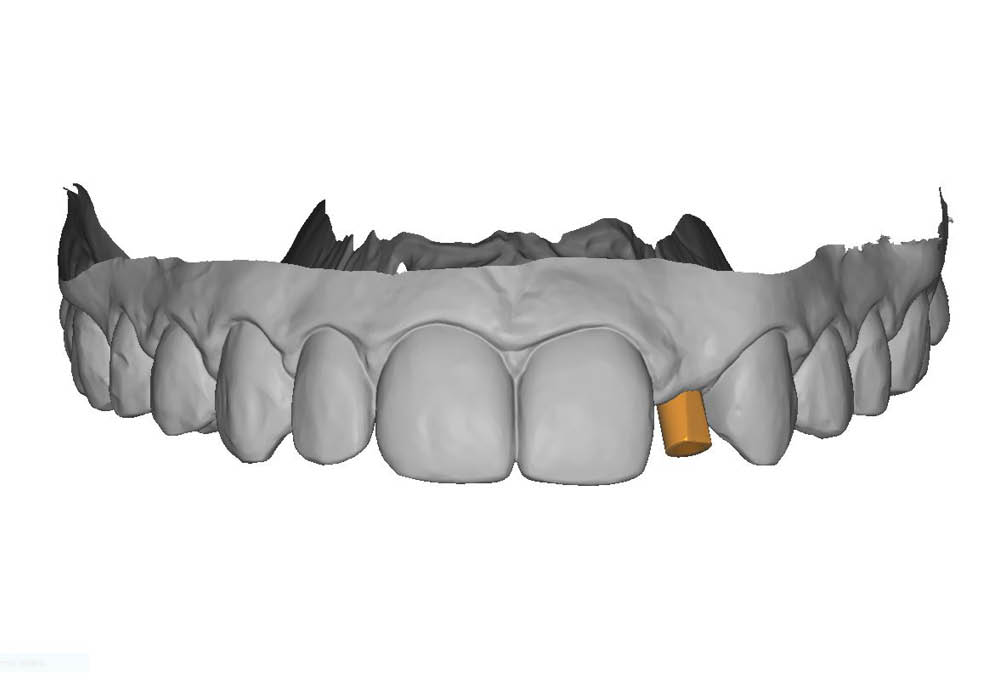

Il primo passaggio ha previsto la valutazione dell’area edentula e la pianificazione implantare.

In questo caso, la particolarità è rappresentata dalla scarsa distanza tra la posizione ideale dell’impianto e le radici degli elementi adiacenti, un aspetto che ha richiesto massima attenzione nella scelta dell’asse e nella valutazione dei volumi disponibili.

La pianificazione chirurgica ha previsto un’analisi tridimensionale dettagliata del sito implantare, valutato sia da angolazioni multiple sia in visione frontale diretta.

L’obiettivo era quello di definire con precisione posizione, profondità e inclinazione dell’impianto, tenendo conto della vicinanza delle radici adiacenti e della necessità di preservare un adeguato spessore vestibolare.